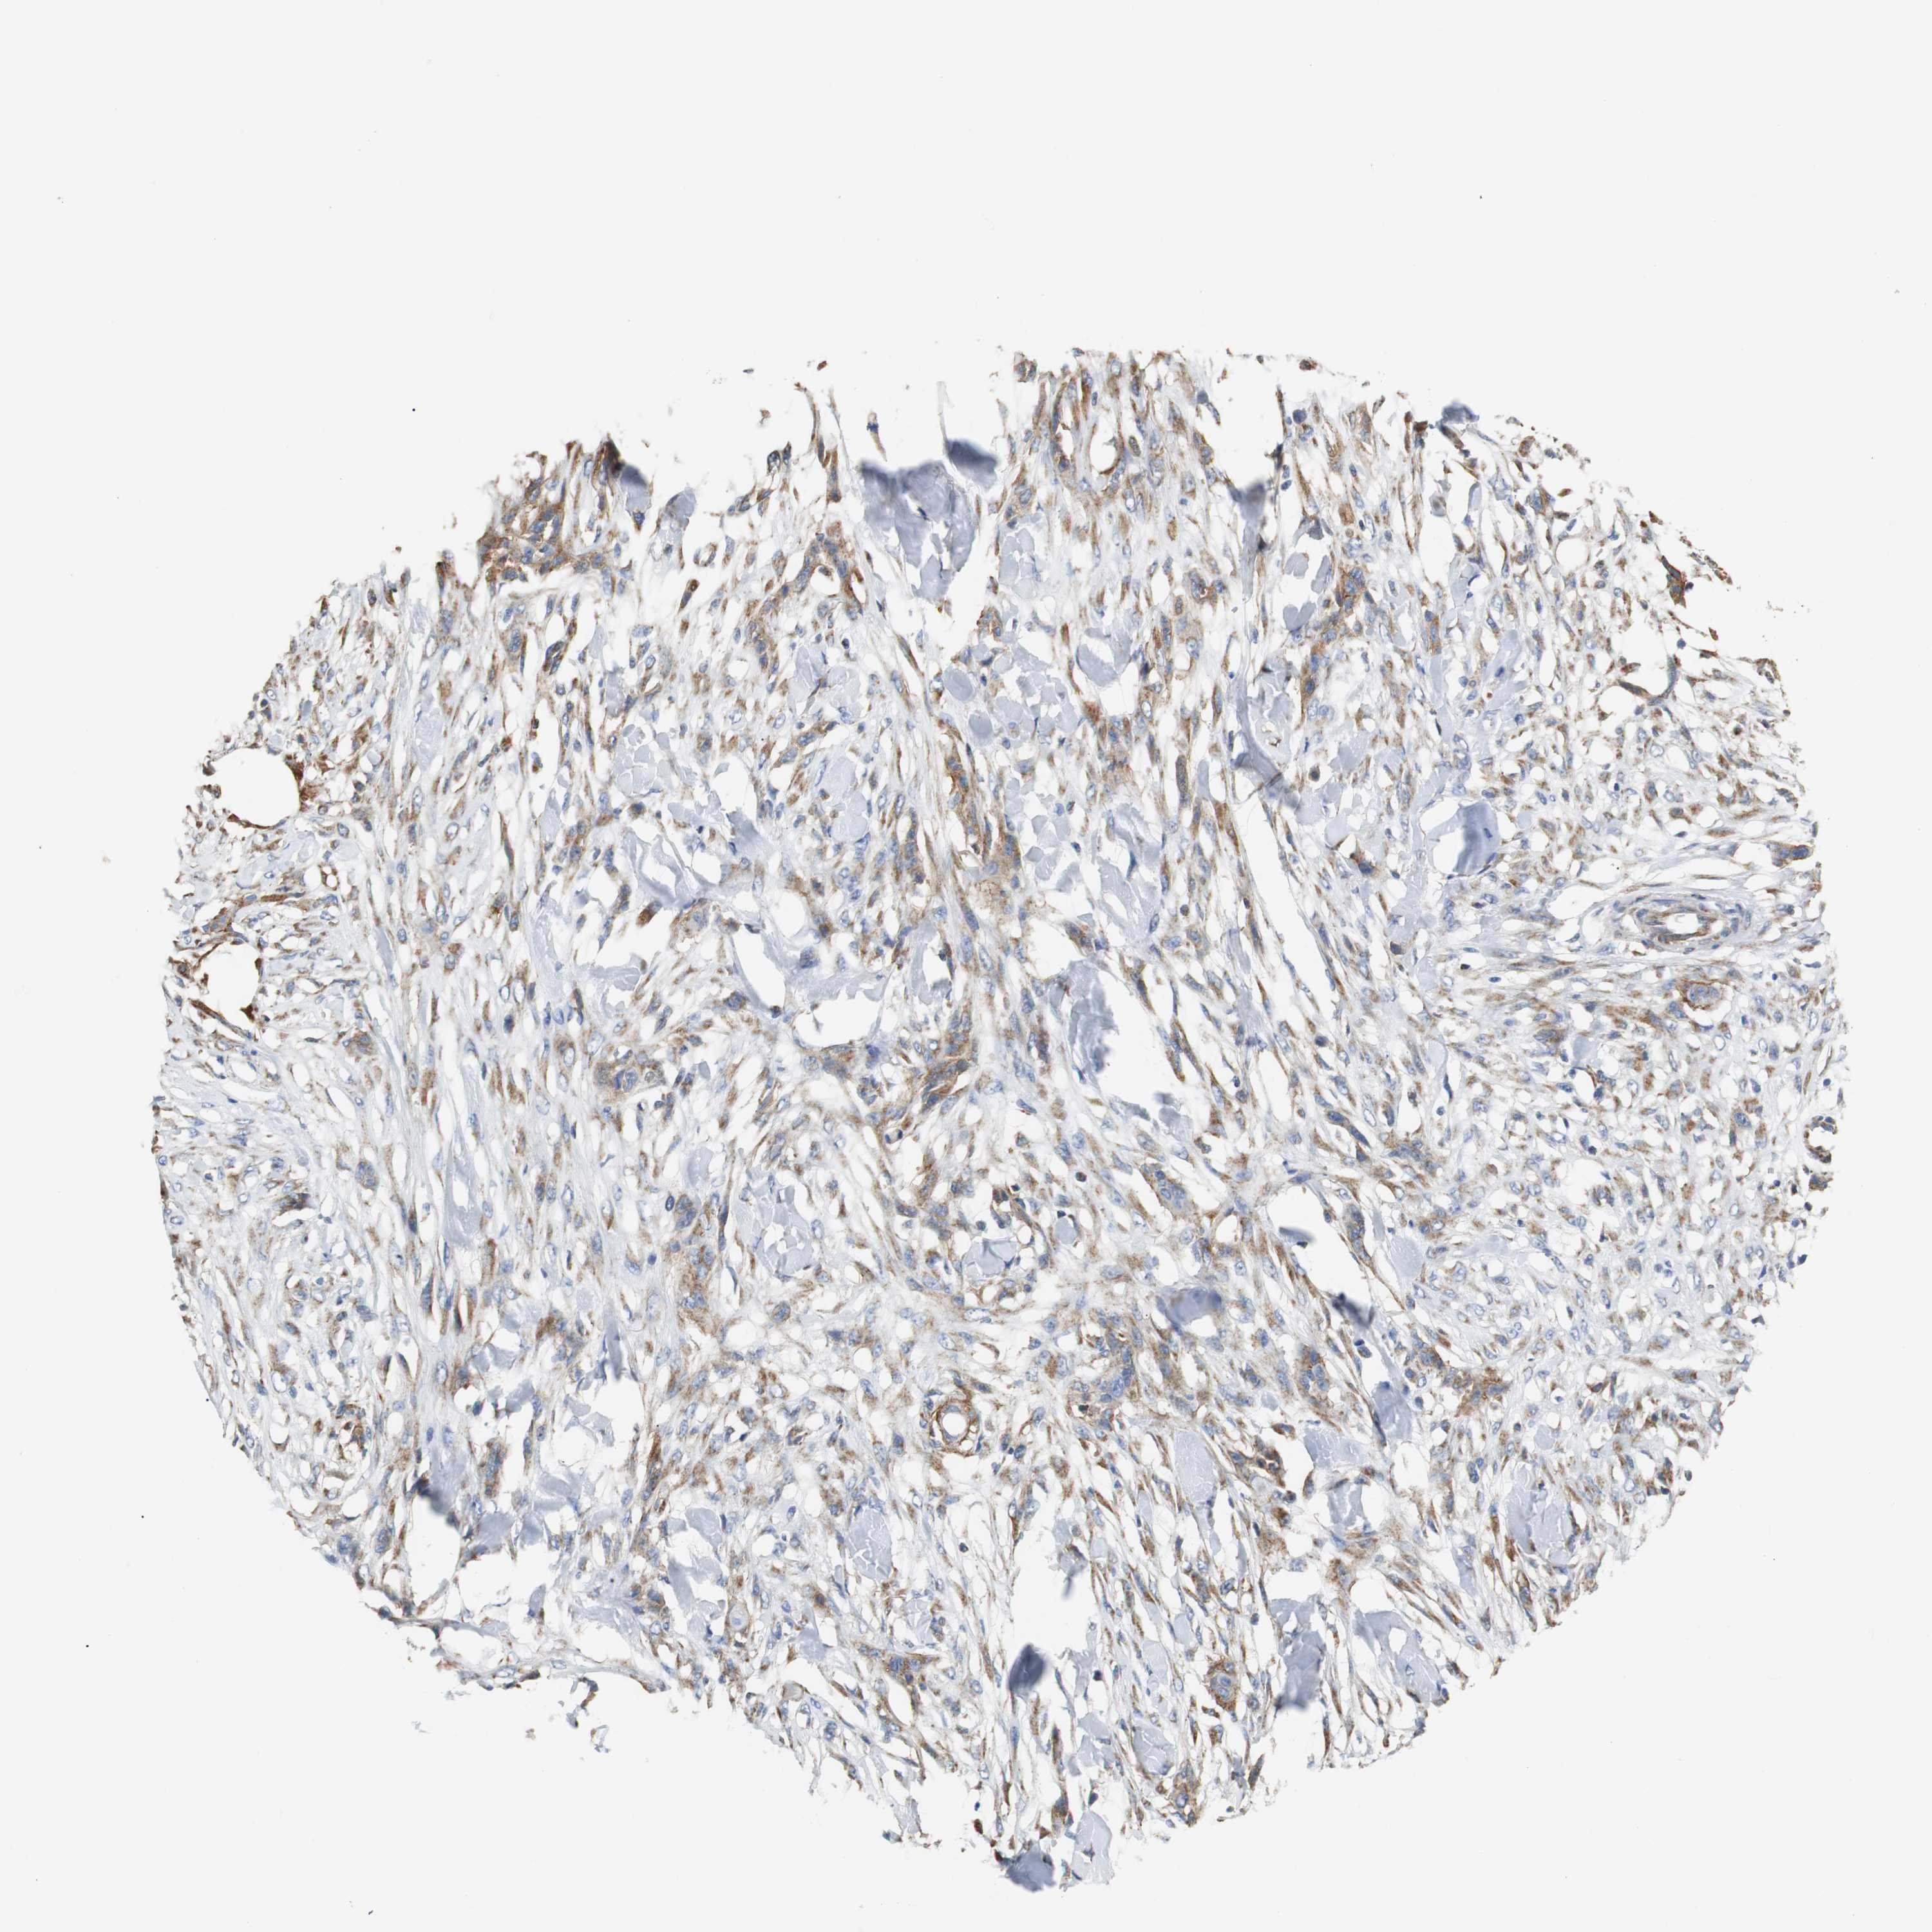

SKIN CANCER - Protein expressioni

A mouse-over function shows sample information and annotation data. Click on an image to view it in a full screen mode. Samples can be filtered based on level of antibody staining by selecting one or several of the following categories: high, medium, low and not detected. The assay and annotation is described here.

Each image is clickable and will lead to virtual microscopy that enables deeper exploration of all samples and also displays staining intensity scores, fraction scores and subcellular localization as well as patient and tissue information for each sample.

Antibody HPA006277

Antibody HPA006507

Antibody CAB017027

Staining

High

Medium

Low

Not detected

Intensity

Strong

Moderate

Weak

Negative

Quantity

>75%

75%-25%

<25%

None

Location

Nuclear

Cytoplasmic/membranous

Cytoplasmic/membranous,nuclear

Squamous cell carcinoma, metastatic, NOS